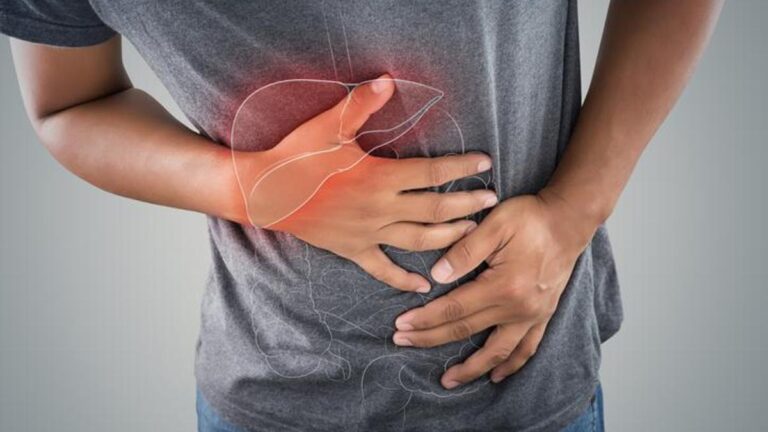

Siroz belirtileri nelerdir? Sirrozu nasıl anlarsınız? Tedavi yöntemleri nelerdir?